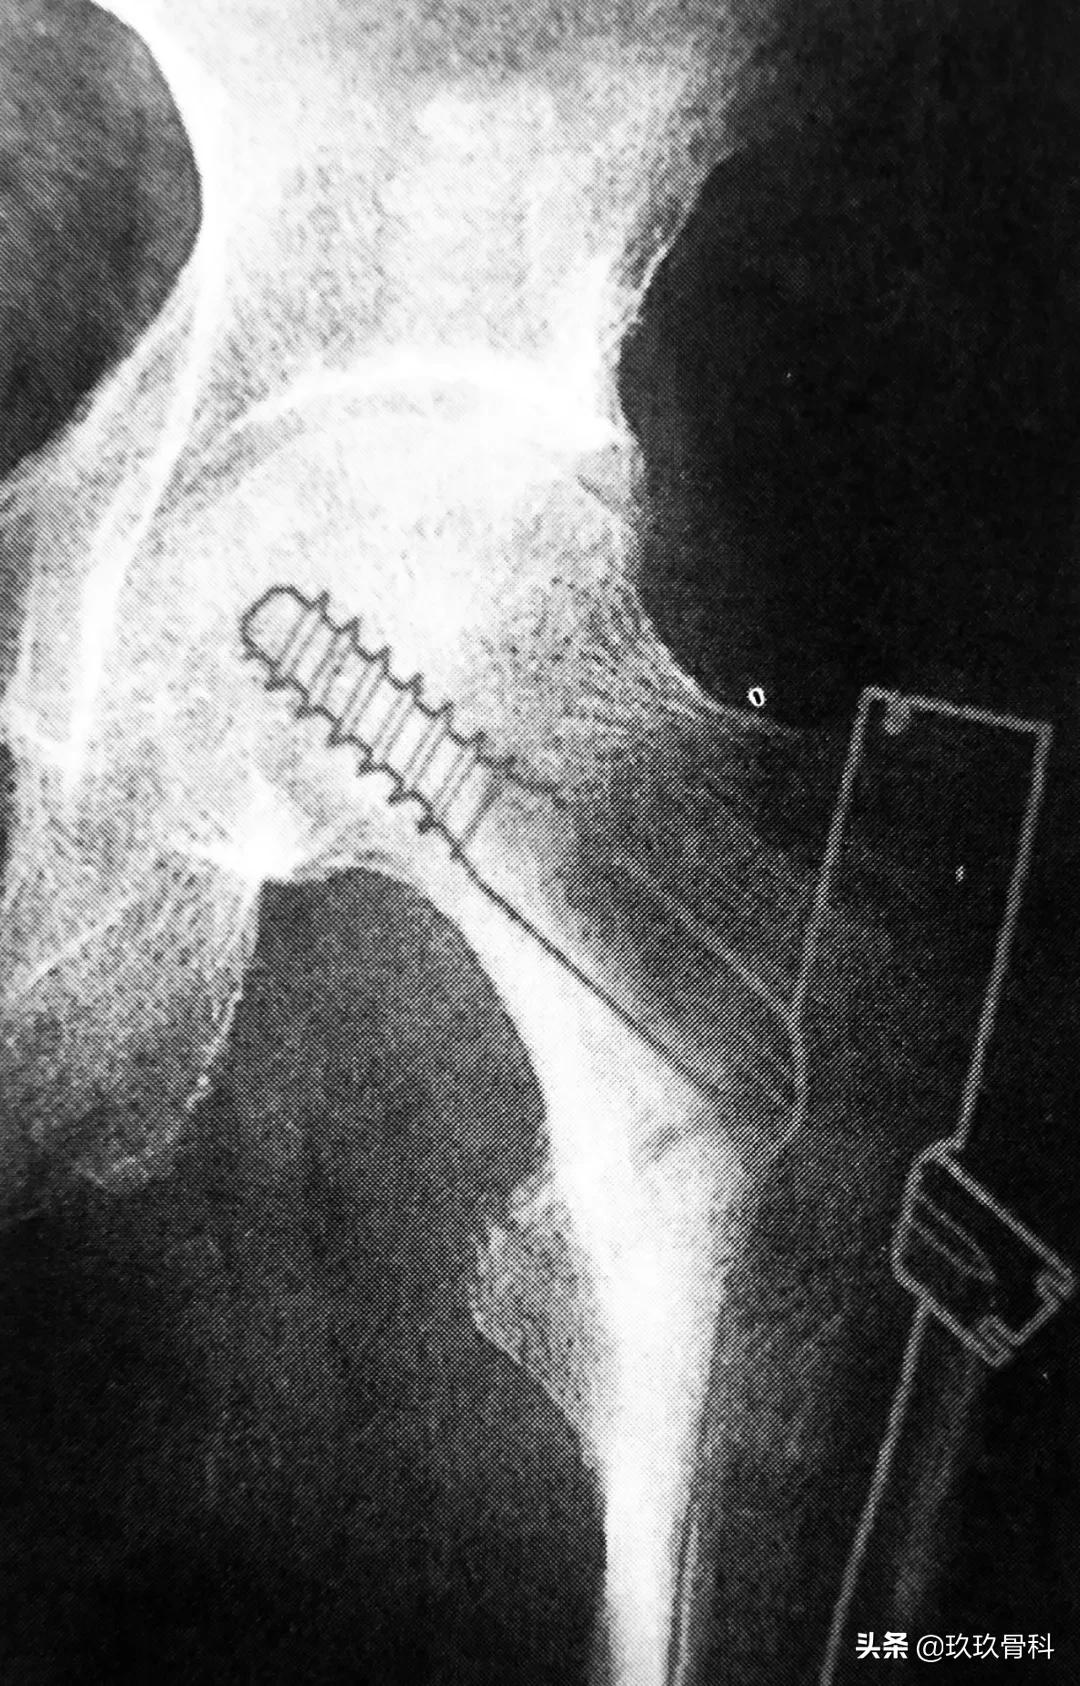

1. Gamma 钉

Gamma 钉适用于股骨颈基底至小转子水平以上的各种类型的骨折。Gamma 钉内固定技术除感染外无绝对禁忌证,伴有严重骨质疏松患者术后的早期活动需要一定的限制。

拉力螺钉的正确放置非常重要,其前提是首先安放好导针的位置,即正位必须与股骨颈轴线重叠或位其稍下方,侧位或斜位导针应在股骨颈中心。

A 拉力螺钉的安装;B 拉力螺钉的正确位置

拉力螺钉的置入,A 确定长度;B 阶梯钻钻孔 C 拧入拉力螺钉并加压

正位拉力钉导针位置、侧位拉力钉导针位置

阶梯钻钻孔、正位拉力钉位置

侧位拉力钉位置、远端锁钉置入